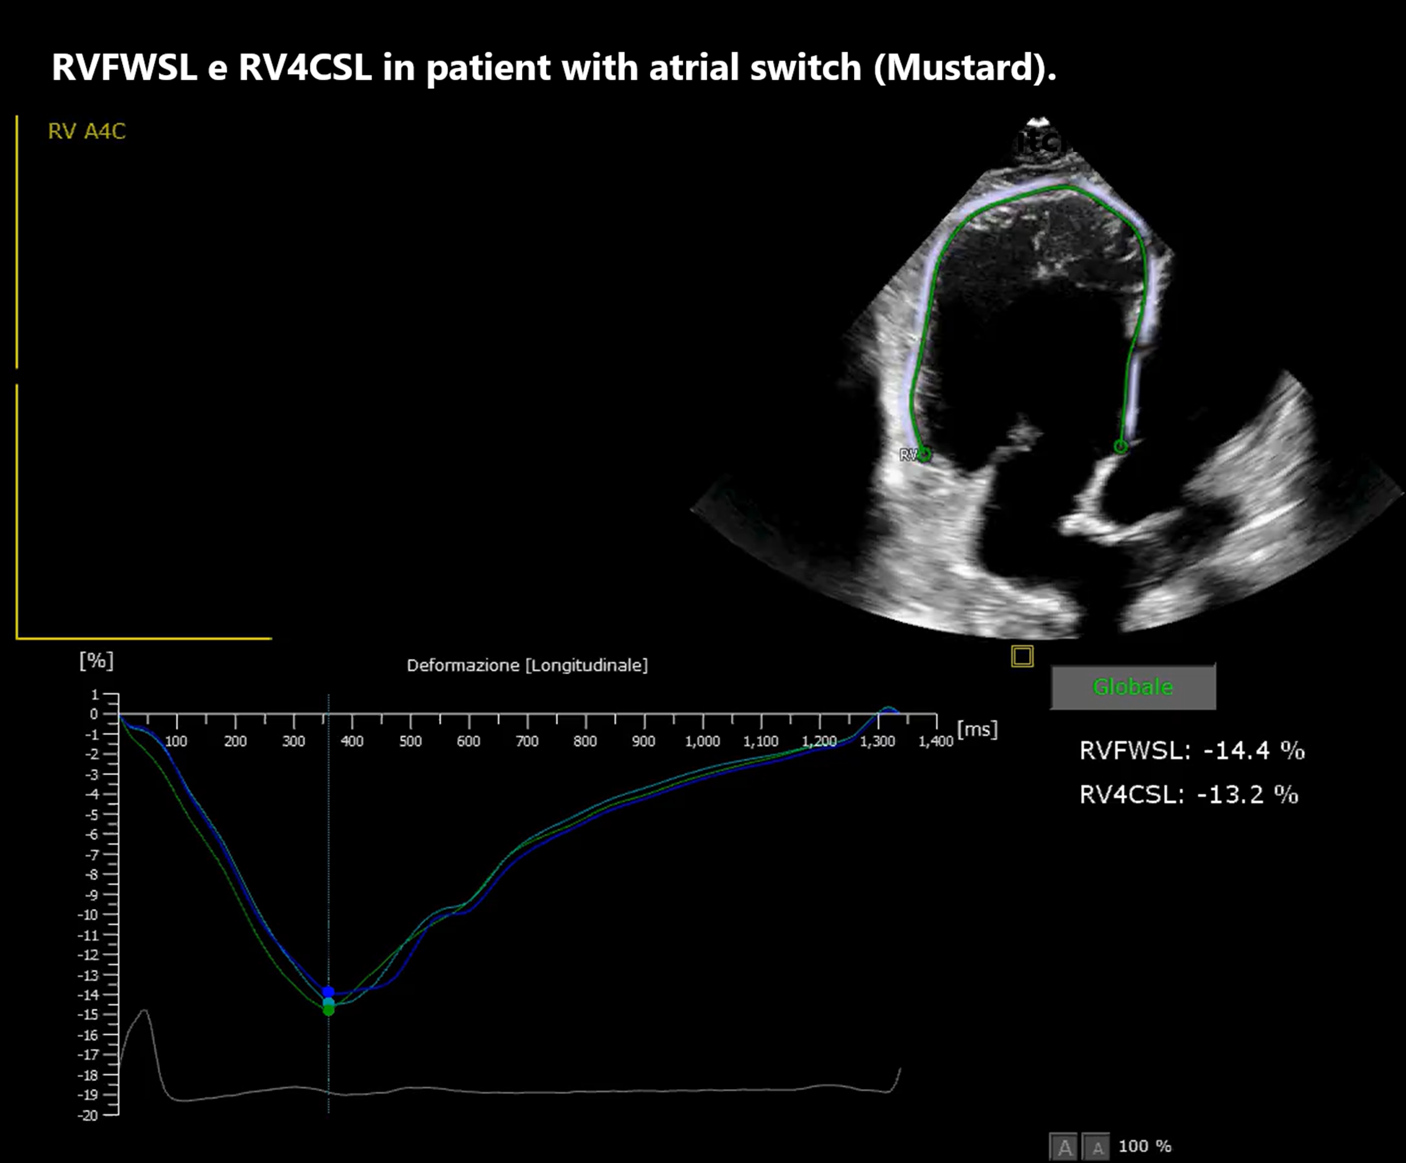

Background: The systemic right ventricle (sRV), present in patients with d-TGA after atrial switch and in congenitally corrected TGA (ccTGA), is chronically pressure-loaded, leading to ventricular remodeling and progressive dysfunction. In this setting, markers of myocardial mechanics and wall stress integrating imaging and biomarkers are useful. Aim: To evaluate the association between NT-proBNP and sRV longitudinal strain (four-chamber strain, RV4CSL, and free-wall strain, RVFWSL) and, secondarily, to describe its relationship with conventional echocardiographic indices (FAC, TAPSE, TDI S′) in a GUCH cohort with sRV in biventricular circulation (Mustard/Senning and ccTGA). Methods: Retrospective study of 20 patients followed at our Center (ARNAS Civico–Di Cristina, Pediatric Cardiology Unit). All underwent comprehensive clinical assessment with functional evaluation, laboratory testing, ECG/Holter and echocardiography; speckle-tracking strain was available in 13/20 patients. Associations were explored using linear models and Pearson correlation; NT-proBNP was also log-transformed (log10) and results were checked with Spearman as a sensitivity analysis for outliers. Results: In patients with complete echocardiographic strain and NT-proBNP data (n=13), RVFWSL was inversely associated with NT-proBNP (Pearson r=−0.555; p=0.049; Spearman ρ=−0.527; p=0.064), suggesting that reduced longitudinal deformation (less negative strain values) is accompanied by greater neurohormonal activation. RV4CSL also showed a consistent inverse association with NT-proBNP (Pearson r=−0.509; p=0.076; Spearman ρ=−0.591; p=0.033), with less negative RV4CSL values associated with higher NT-proBNP. As a complementary analysis, higher FAC was associated with higher absolute RV4CSL (r=0.624; p=0.023), whereas TAPSE and TDI S′ showed weaker but concordant associations. Conclusions: In our biventricular-circulation sRV cohort, higher NT-proBNP is associated with worse longitudinal mechanics, particularly at the free wall. Interpreted together, strain and NT-proBNP may help grade hemodynamic severity and guide follow-up; these exploratory findings require confirmation, using additional diagnostic modalities.